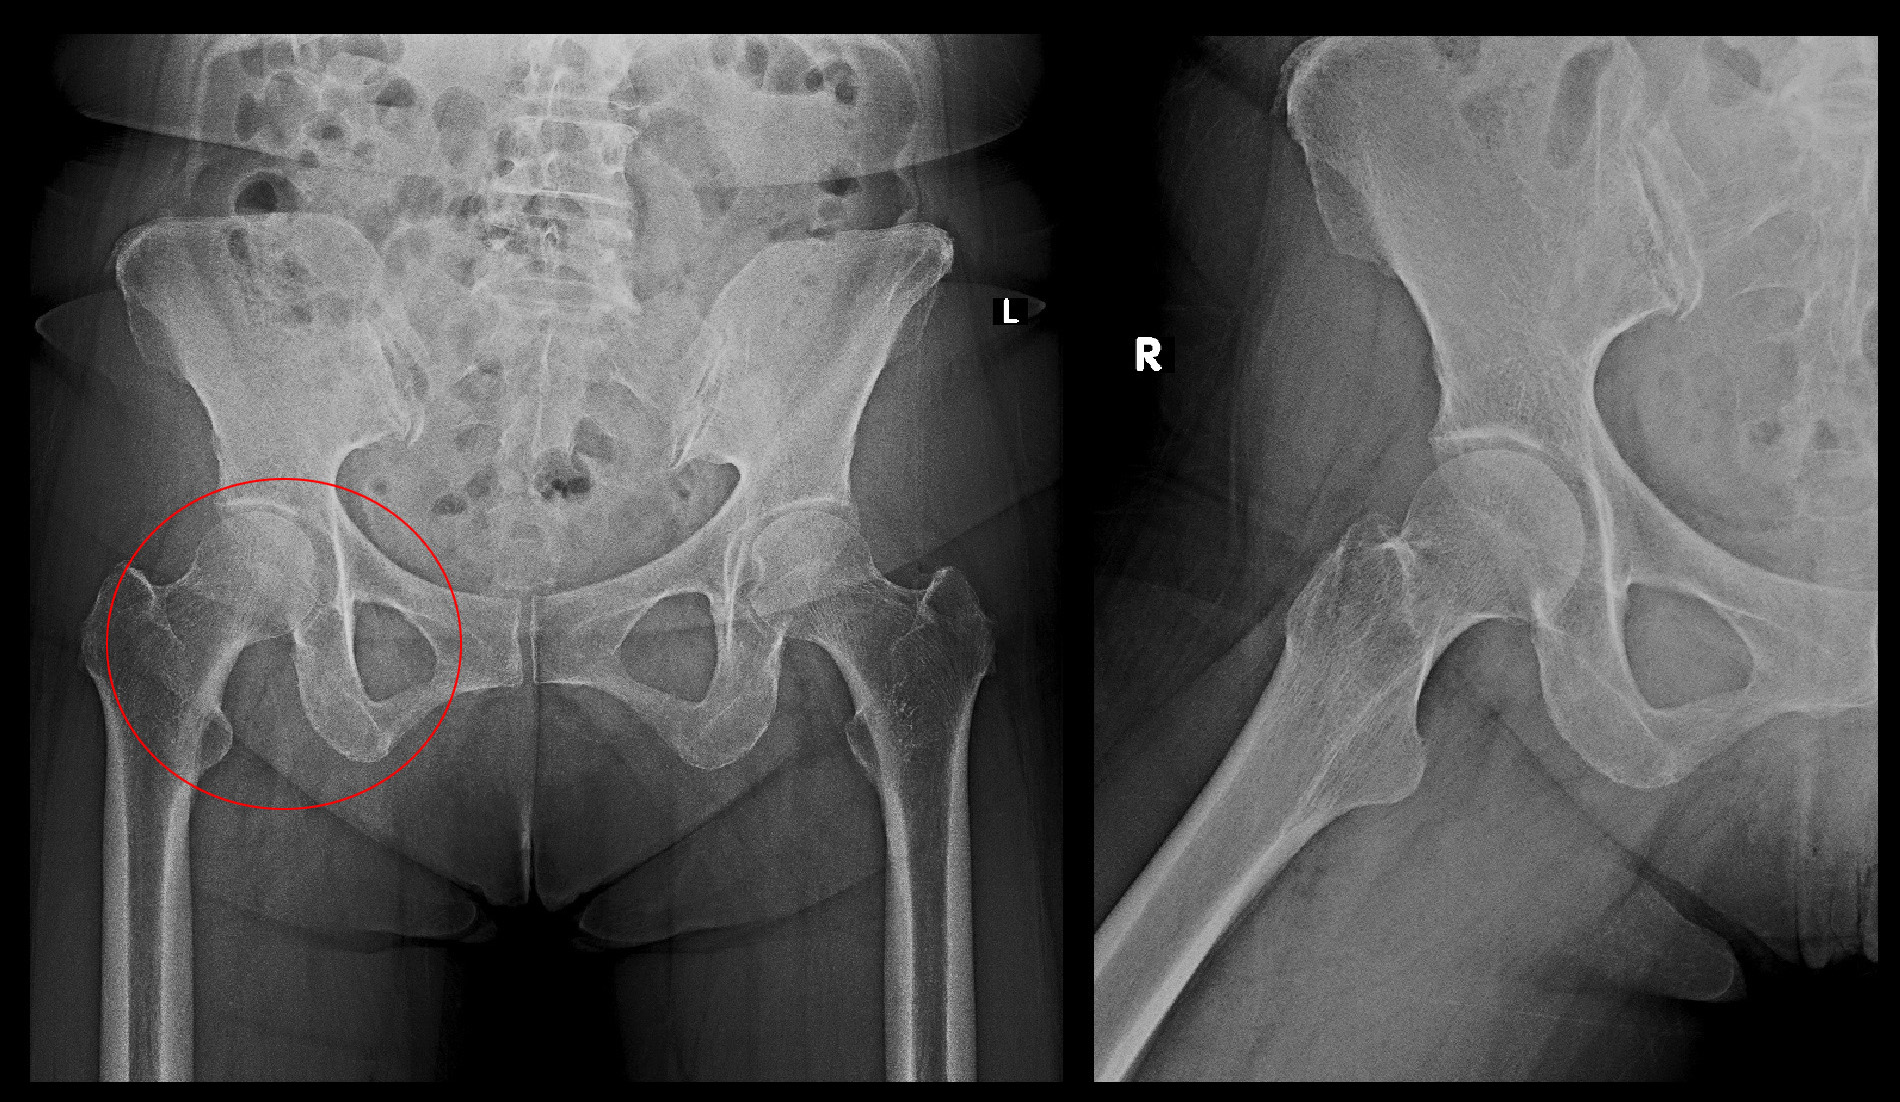

開業当初のMRIでの画像で今より画質悪いものですが、診断は十分可能です。L4-5とL5-Sに椎間板ヘルニアを認めすが、L4-5の方が脊髄(腰の背中側に長くつながっている領域です)の圧迫は強いと判断し、左L5神経根ブロックを勧めました。しかし患者さんは、以前他の整形外科でブロックを受け、失神しそうなほどの痛みがあったので、絶対いやだと断られました。そこで臀部に局注(ブロックのパンフレットの④トリガーポイント注射となります)を施行し、鎮痛剤を処方しました。

次の患者さんは83才の女性です。平成27年10月30日車いすで受診されました。同年5月14日から9月21日まで整形外科病院に腰痛と両下肢の鈍痛(坐骨神経痛です)で歩行困難となり入院していたけれど、症状は軽減せず歩行可能とはならなかったとのことでした。腰椎MRI検査ではL3-4高位で重度の脊髄圧迫(脊柱管狭窄と表現します)を認めました。これが腰痛と両下肢の鈍痛の病因です。

腰椎MRI検査では、L3-4とL4-5に軽度の椎間板ヘルニアを認めますが、中央上段のT1矢状断の右よりの画像でL3-4のヘルニアの方がL4-5のヘルニアより白っぽく目立ちます。これはL4-5ヘルニアが最近悪化したことを示す所見です。股関節痛は坐骨神経痛ととらえられるので、おそらく服薬では症状の軽減がえられないため、神経根ブロックを勧めましたが、患者さんは希望されませんでした。そのため鎮痛剤と筋弛緩剤を1週分処方しました。